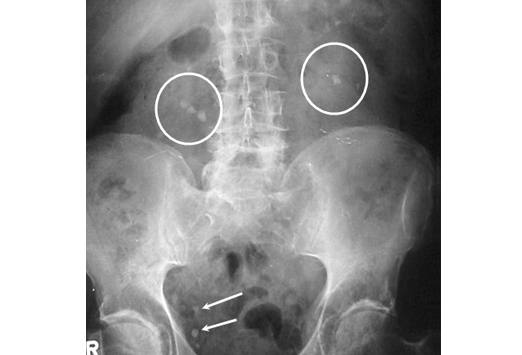

Под мочекаменной болезнью понимают возникновение камней в одном из отделов мочевого тракта, включающего в себя почки, мочеточники, мочевой пузырь. Почечные камни – это химические вещества в моче, которые при определённых условиях выпадают в осадок и превращаются в кристаллы (чаще всего соли кальция) с острыми концами.

Как проводится диагностика мочекаменной болезни?

Жалобы на боль указанной выше локализации могут возникать не только при почечной колике, но и при воспалении почек или мочевого пузыря, при поражении кишечника или половых органов. Поэтому только на основе жалоб, самой постоянной из которых является жалоба на нестерпимую боль, поставить точный диагноз нельзя. Для этого врач проводит дополнительные исследования: